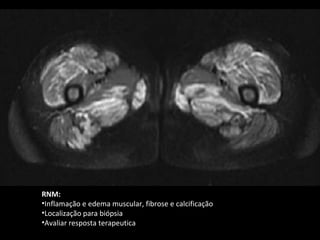

RNM:

•Inflamação e edema muscular, fibrose e calcificação

•Localização para biópsia

•Avaliar resposta terapeutica